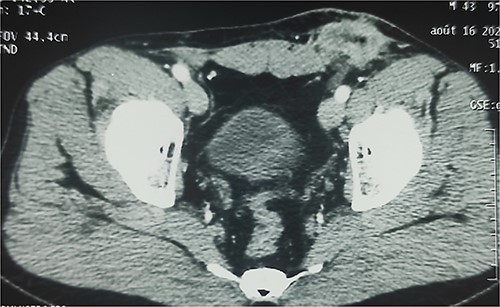

A 38-year-old patient visited our department with a purulent discharge from an inflammatory mass in the left inguinal region. He had a history of mesh repair for a left inguinal hernia performed in another hospital eight years before his admission to our hospital. Hernia repair was performed as part of a humanitarian surgical outreach. Patient experienced pain and reported purulent discharge from the surgical wound, two months after the operation. This complication was treated with local care and antibiotic therapy, the nature of which is not specified. The infection persisted despite the treatment. A second operation performed two years after the first one, allowed partial removal of the infected mesh and temporary remission of the symptoms. Apart from the surgical history, the patient had no known pathological history and was neither a diabetic nor a smoker. On admission to our department, his general condition was preserved, the body mass index was 25 kg/m2 and body temperature was 37.5°C. On examination of the left inguinal region, an inflammatory and painful mass was noted with several fistulous orifices through which pus flowed easily under pressure (Fig. 1). External genitalia and other clinical examinations were normal. Laboratory blood tests were normal, except for an elevated CRP level of 52 mg/mL. Methicillin-resistant Staphylococcus aureus was isolated from the pus culture. A CT scan performed after a contrast injection showed a relatively well-limited mass with heterogeneous enhancement and central hypodensity related to the mesh (Fig. 2). En bloc removal of the mass and infected mesh was indicated. The procedure was performed under spinal anesthesia. The elements of the spermatic cord were intimately adherent to the mass, making the dissection laborious. The excision was completed with en bloc removal of the inflammatory mass (Fig. 3). Further pathological examination of the surgical specimen revealed an inflammatory granuloma without cellular atypia, compatible with a foreign body reaction. The inguinal wound was closed with a suction drain and left in place for 7 days. On the third post-operative day, a scrotal swelling appeared, and on the tenth day, there was an abundant flow of pus throughout the inguinal wound. Scrototomy allowed the diagnosis of ischemic necrosis of the left testicle. An orchiectomy was performed, and the patient received local care for the surgical wound until complete healing was achieved in 27 days. The surgical wound had healed completely one year post-operatively, indicating effective evolution. The examination revealed no signs of hernia recurrence.

Enhanced CT scan showing well-limited mass in the left inguinal region with heterogeneous enhancement and central hypodensity related to the infected mesh.